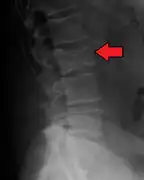

The diagnostic examination of a person with suspected multiple myeloma typically includes a skeletal survey. This is a series of X-rays of the skull, axial skeleton, and proximal long bones. Myeloma activity sometimes appears as "lytic lesions" (with local disappearance of normal bone due to resorption) or as "punched-out lesions" on the skull X-ray ("raindrop skull"). Lesions may also be sclerotic, which is seen as radiodense.[76] Overall, the radiodensity of myeloma is between −30 and 120 Hounsfield units (HU).[77] Magnetic resonance imaging is more sensitive than simple X-rays in the detection of lytic lesions, and may supersede a skeletal survey, especially when vertebral disease is suspected. Occasionally, a CT scan is performed to measure the size of soft-tissue plasmacytomas. Nuclear Medicine Bone scans are typically not of any additional value in the workup of people with myeloma (no new bone formation; lytic lesions not well visualized on nuclear bone scan).

X-ray of the forearm, with lytic lesions

Bone pain affects almost 70% of people with multiple myeloma and is one of the most common symptoms.[2]: 653 [23] Myeloma bone pain usually involves the spine and ribs and worsens with activity. Persistent, localized pain may indicate a pathological bone fracture. Involvement of the vertebrae may lead to spinal cord compression or kyphosis. Myeloma bone disease is due to the overexpression of receptor activator for nuclear factor κ B ligand (RANKL) by bone marrow stroma. RANKL activates osteoclasts, which resorb bone. The resultant bone lesions are lytic (cause breakdown) in nature, and are best seen in plain radiographs, which may show "punched-out" resorptive lesions (including the "raindrop" appearance of the skull on radiography). The breakdown of bone also leads to the release of calcium ions into the blood, leading to hypercalcemia and its associated symptoms.[24]